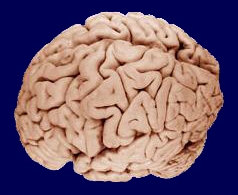

يشكل يشكل 85% من إجمالي وزن الدماغ. ويقسم شق كبير يسمى الشق الطولي المخ إلى نصفين يسميان نصف الكرة المخية الأيمن ونصف الكرة المخية الأيسر. ويتصل النصفان بحزم من الألياف العصبية ، يسمى أكبرها الجسم الثفني. وينقسم كل نصف بدوره إلى أربعة فصوص، يسمى كل منها باسم عظمة الجمجمة التي تقع فوقه. والفصوص هي:

وتكوِّن شقوق في القشرة المخية الحدود بين هذه الفصوص. والشقان الرئيسيان هما الشق المركزي والشق الجانبي.

وتكوِّن طبقة رقيقة من الخلايا العصبية تسمى [[القشرة المخية أو القشرة الجزء الخارجي من المخ. ويتكون معظم المخ تحت القشرة من ألياف من الخلايا العصبية. وتربط بعض هذه الألياف أجزاء القشرة بعضها ببعض، بينما تربط ألياف أخرى القشرة بالمخيخ وجذع الدماغ والحبل الشوكي.

والقشرة المخية مطوية في شكل سطح كثير النتوءات والأخاديد. ويزيد هذا الطي المساحة السطحية للقشرة، وعدد الخلايا العصبية التي تحتويها في الفراغ المحصور بالجمجمة. وتستقبل بعض مناطق القشرة المخية، المسماة القشرة الحسية الرسائل القادمة من الأعضاء الحسية، بالإضافة إلى رسائل اللمس ودرجة الحرارة من أجزاء الجسم المختلفة. وترسل مناطق في الفص الجبهي تسمى القشرة الحركية، الدفعات العصبية التي تتحكم في الحركات الإرادية لكل العضلات الهيكلية. وأكبر أجزاء القشرة حجمًا هو قشرة الترابط، حيث يحتوي كل فص على قشرة ترابط يحلل المعلومات ويعالجها ويخزنها. وقشرات الترابط هي التي تمكِّن الشخص من أداء النشاطات التي تتطلب قدرات عالية مثل التفكير والتحدث والتذكر.